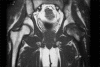

Figure 1

Coronal T1-weighted image shows homogeneously hypointense marrow edema with medial sparing of the left femoral head